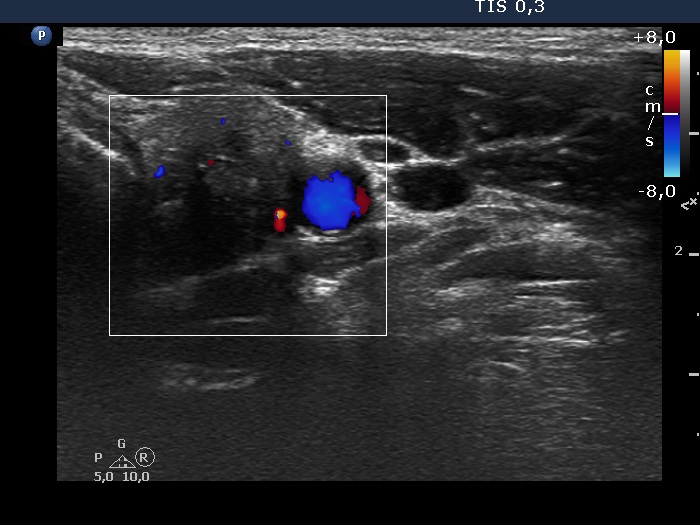

The composition of the nodule - case 126

Six weeks after the last session of sclerotherapy (ultrasonographic picture 4)

Left lobe, transverse scan, color Doppler mode. The vascularization is decreased.